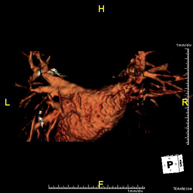

- Angio-RM Aorta Torácica

Prueba diagnóstica no invasiva que consiste en la obtención de imágenes de alta definición anatómica de la aorta torácica (principal arteria del tórax) mediante el empleo de un campo electromagnético y ondas de radio (con un emisor y un receptor). No utiliza radiación ionizante. En la mayoría de los casos es necesario el empleo de contraste paramagnético (Gadolinio). Permite un estudio angiográfico no invasivo gracias a la inyección de Gadolinio, con posterior reconstrucción en 2D y 3D gracias a estaciones de trabajo especializadas. También incluye el estudio de la válvula aórtica, información imprescindible en el caso que el paciente necesite cirugía. Esta prueba está especialmente indicada en pacientes que requieren tratamiento quirúrgico (como el mapa vascular pre-quirúrgico), en el seguimiento de pacientes con aneurismas de aorta, etc.